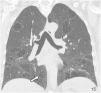

High-resolution computed tomography (HRCT) is the imaging method of choice for the evaluation and diagnosis of interstitial lung diseases because it confirms the presence of lung disease and establishes the correct diagnosis for associated complications. Nevertheless, the definitive diagnosis of these entities requires the imaging findings to be interpreted together with their clinical manifestations and histological confirmation. In this group of diseases, HRCT findings play a fundamental role, being especially important for avoiding unnecessary biopsies. For these reasons, clinicians need to be familiar with the basic radiologic patterns associated with this group of lung diseases: septal, reticular, nodular, ground-glass, cystic, and consolidations. This chapter describes the features of these patterns and ways that they can present, and it reviews some of the most common interstitial lung diseases, emphasizing the predominant radiologic patterns in each of them.

La tomografía computarizada de alta resolución (TCAR) es el método de imagen de elección en la evaluación y el diagnóstico de las EPID, ya que confirma la presencia de enfermedad pulmonar y establece el correcto diagnóstico de las complicaciones asociadas. No obstante, el diagnóstico definitivo de estas enfermedades requiere la concordancia con las manifestaciones clínicas y la comprobación anatomopatológica. Las imágenes radiológicas obtenidas por la TCAR en este grupo de enfermedades tienen un papel fundamental, de especial importancia para evitar la realización de biopsias innecesarias. Por estas razones, el médico clínico debe familiarizarse con los patrones radiológicos básicos asociados a este grupo de enfermedades pulmonares: septal, reticular, nodular, en «vidrio deslustrado», quístico y de condensación. En este capítulo se describen las características y la forma de presentación de estos patrones, y se revisan algunas de las EPID más frecuentes, haciendo hincapié en los patrones radiológicos predominantes en ellas.